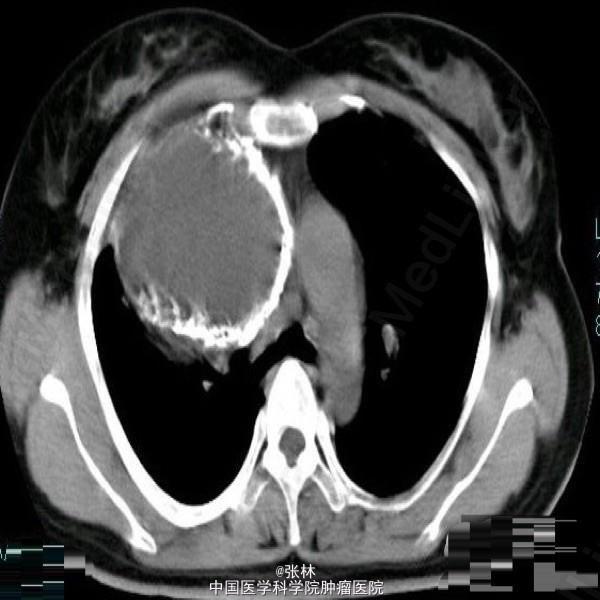

【临床病史】:患者,女性,37岁,运动后心慌、胸闷三年。右胸部呼吸音消失。叩诊呈实音。X线:右侧胸腔占位。 【影像表现】:右侧胸腔巨大囊性低密度影,大小约为109mmx118mm,边界清晰,边缘可见蛋壳样钙化,密度不均匀,CT值-35-420HU。 【影像诊断】:纵隔畸胎瘤 【最后诊断】:病理诊断:前纵隔囊性成熟性畸胎瘤。 【讨论】:畸胎类肿瘤分为囊性和实性两类,囊性畸胎瘤即皮样囊肿,多发生在前纵隔,CT为诊断该肿瘤最佳的影像学方法,可很好地显示肿块内的钙化、骨骼及脂肪成分。